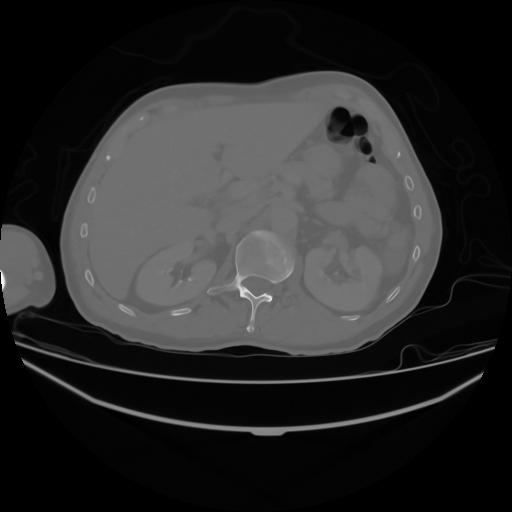

4 CUERPO,CE,Axial,3.0,CUERPO,,